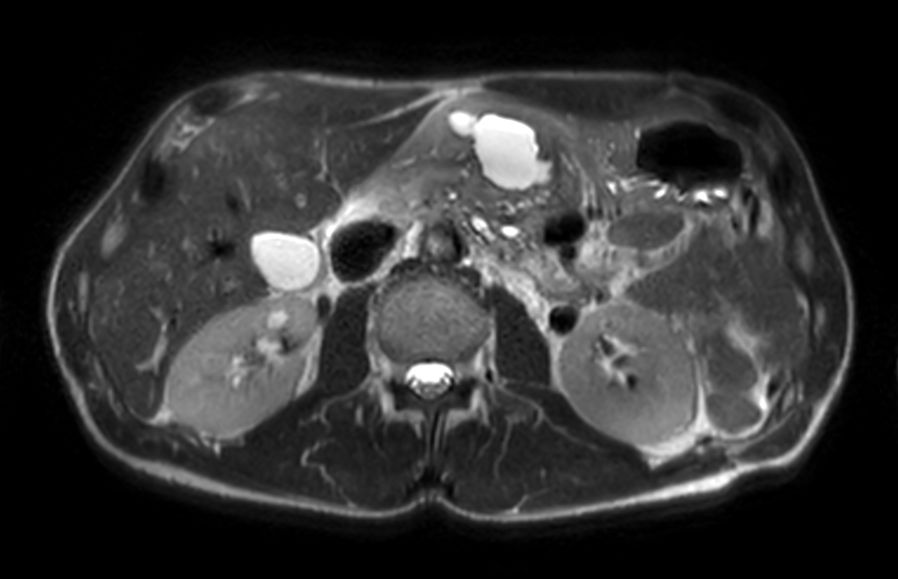

Axial dynamic T1w FFEmDIXON XD